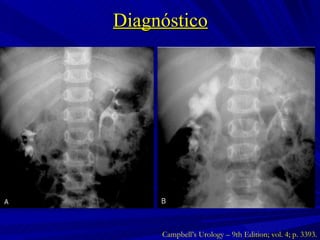

Diagnóstico Campbell’s Urology – 9th Edition; vol. 4; p. 3391.

Diagnóstico Campbell’s Urology – 9th Edition; vol. 4; p. 3393.